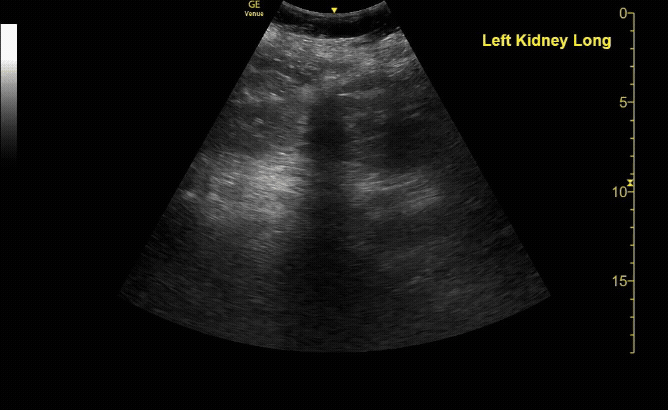

R/L kidney In sagittal (long) view

c/o Victoria Gonzalez, MD